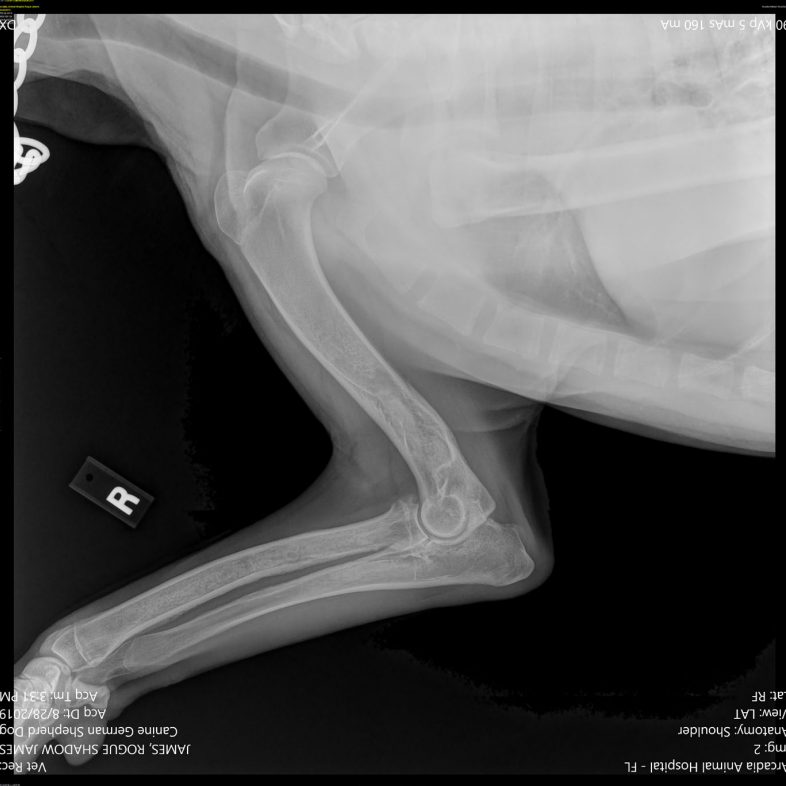

사진 모음

- 범골염, 앞다리 전체 범위

- 골수관의 불규칙 패턴

- 노뼈와 자뼈가 겹쳐보여 구별 어려움 (시험용X)